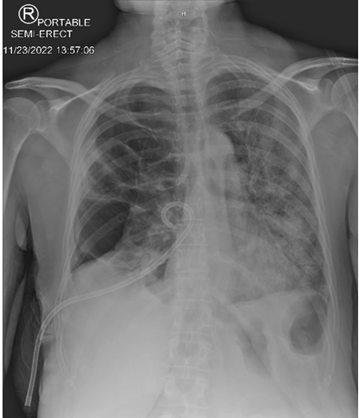

Figure 5: Single view chest X-ray showing post non-surgical chest tube placement with slight improvement of right lung atelectasis.

Figure 6: Serial single view chest X-ray two days post non-surgical chest tube placement showing no significant change in the size of the pneumothorax.